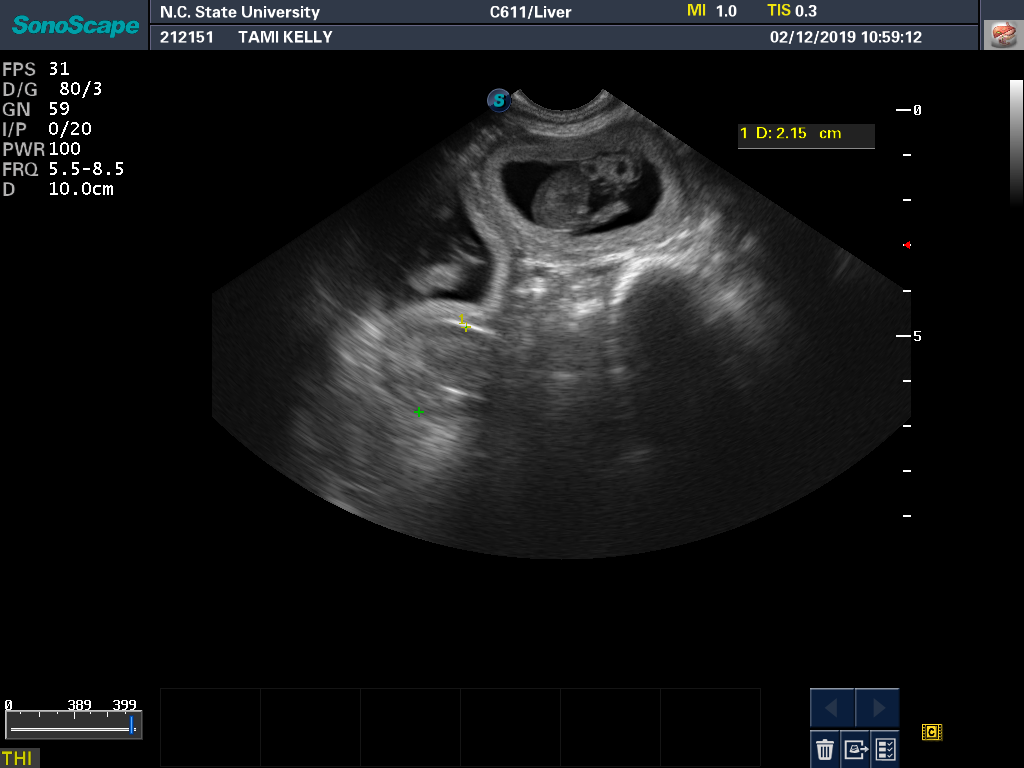

Tami had another ultrasound and progesterone check. All looks well. Here is a a good view of one of the puppies from the ultrasound monitor. And a view showing that there really are three puppies.